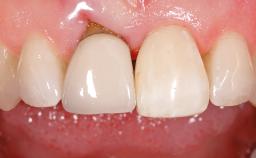

Peri-Implant Mucositis Treatment Outcomes on an Implant with a Submucosal Restoration Margin

Mauricio Araujo and Flauvia Matarazzo present this straightforward clinical case, demonstrating the potential effect of implant placement depth on the resolution of peri-implant treatment. A 42-year-old systemically healthy female patient, a non-smoker with no history of periodontitis, was treated at the Dental Clinic at the State University of Maringá, Brazil between 2008 and 2009, when she received five implants restored with single crowns at sites 14, 26, 27, 36, and 46. After delivery of the implant-supported prosthetic restorations, the patient was enrolled in the supportive peri-implant therapy (SPiT) maintenance program at the same university.